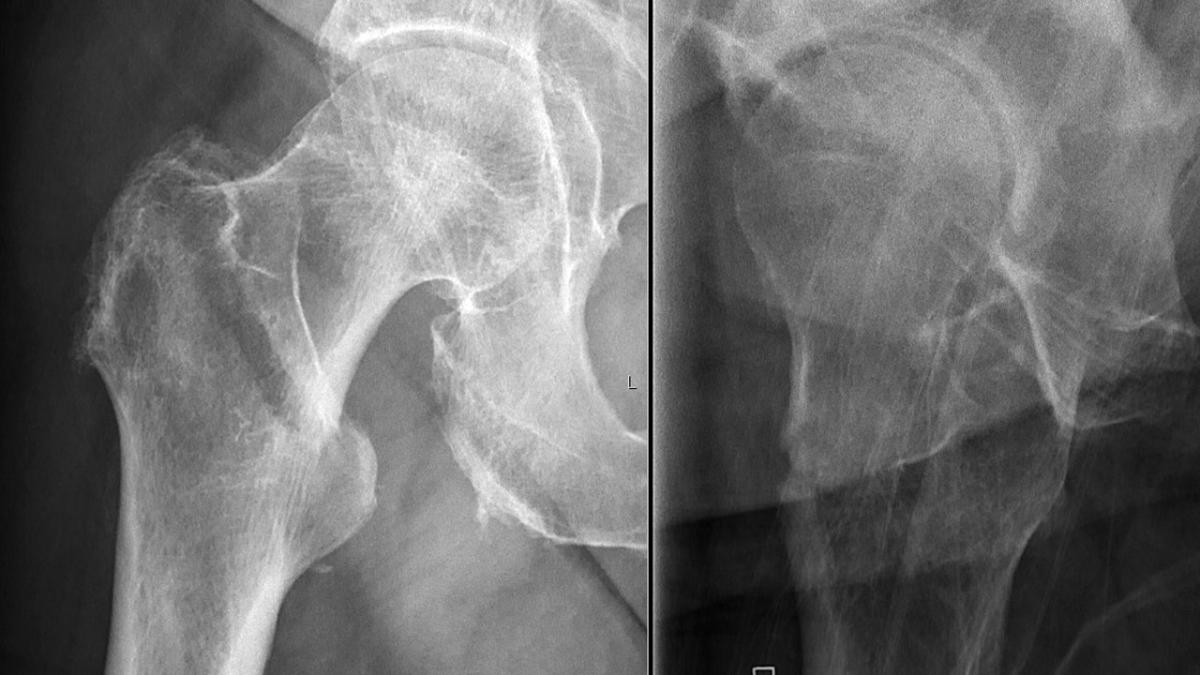

Перелом шейки бедра

В период новогодних праздников количество травм среди граждан России увеличивается минимум на 25%, а в отдельные дни этот показатель может возрасти до 40-45%. Об этом сообщил Алексей Коваленко, главный врач университетской клинической больницы №5 Сеченовского Университета, в интервью ТАСС.

По словам Коваленко, увеличение числа травм в новогодний период связано с несколькими факторами, включая погодные условия. Особенно часто травмы случаются, когда на улице скользко после ледяного дождя, что значительно повышает риск падений и других инцидентов.

"В новогодние праздники минимум на четверть, то есть на 25%, увеличивается число травм в России. А в отдельные дни это количество может возрасти и до 40-45% при комбинации разных факторов", — отметил эксперт.